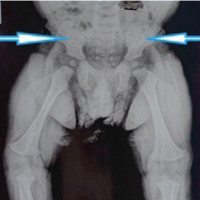

On imaging, complex syndactyly of digits three and four of the left hand and digits four and five of the right hand were also identified (Fig. 2).

Figure 2: Pre-operative posterior-anterior radiographs of the left and right hands demonstrating complex syndactyly of digits three and four of the left hand and four and five of the right hand.